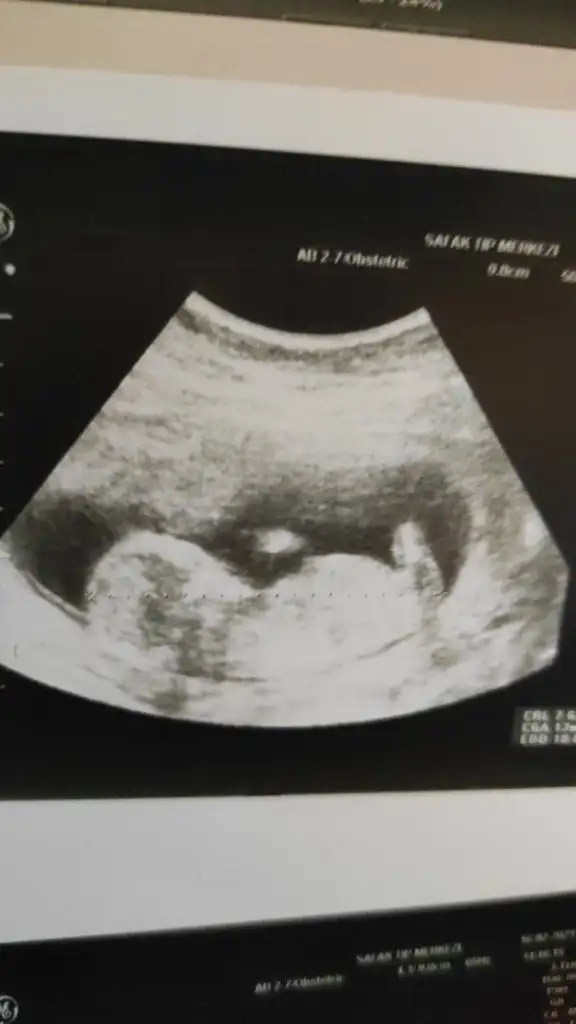

Ay, lütfen bana da yorum yapın karından 6+6 daylenki Ultrasonumuz ☺️

Eklentiler

• IMG_20210217_224509.webp

IMG_20210217_224509.webp

26,3 KB · Görüntüleme: 163